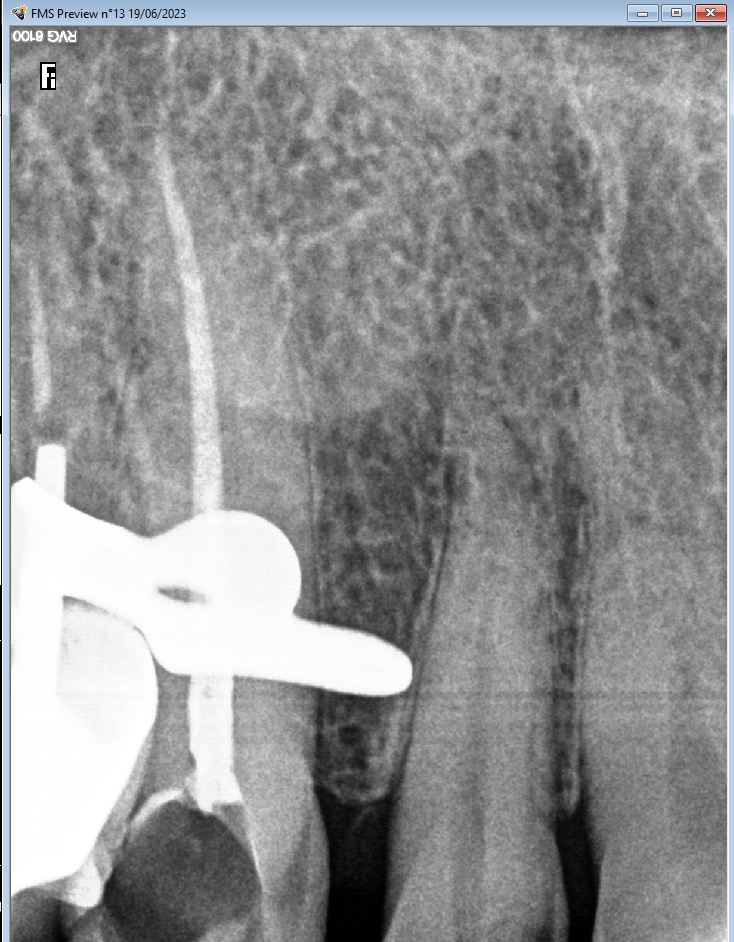

Une histoire de racine fendue ? Tu vois quoi toi, sur les radios ?

Des radios comme ça on en a tous plein nos tiroirs.

Et en endo personne est irréprochable, ...a la vision de la radio .

On peut aussi faire comme le cas des 25/26 que j’ai montré, et là c’est pas la même.